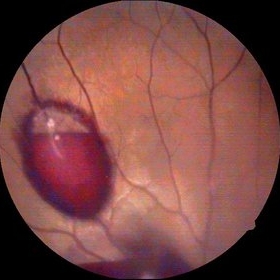

Myopic Degeneration, Macular Hemorrhage

Sep 10 2014 by Mehul A Shah

A 50-year-old male patient presented with complaint of sudden loss of vision.

Photographer: Drashti Netralaya,Dahod

Imaging device: FF 450

Condition/keywords: myopic degeneration